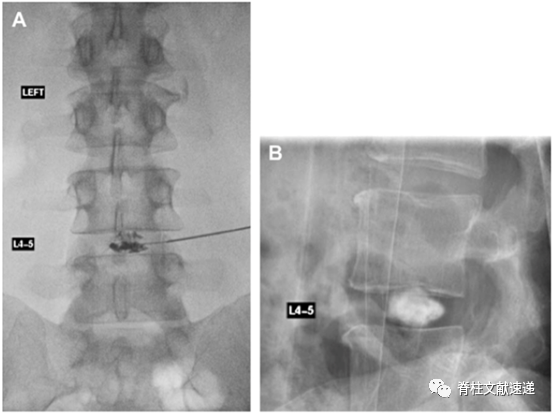

腰椎间盘造影用于鉴别椎间盘源性腰痛。具体操作如下。

4.1. 俯卧位,常规消毒,定位。将穿刺针置入髓核区域,正位片上接近中线,侧位片上亦接近椎间盘中央。

4.2 注入造影剂,使髓核区域填充,此时模拟出日常出现的典型腰痛为阳性。